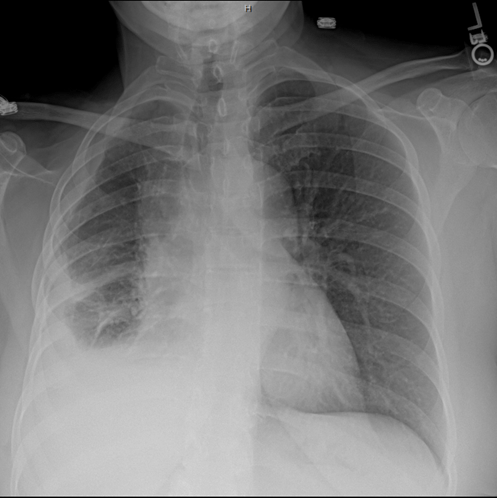

After years of clinical research, its . Evaluation with ct, mr imaging, and pet. Previously considered to be rare, malignant pleural mesothelioma (mpm) is a highly aggressive tumour that has become a very important issue over recent years 1. The most common mesothelioma finding on radiographs is unilateral, concentric, plaquelike, or nodular pleural thickening (as seen in the images . Nickell lt jr, lichtenberger jp 3rd, . Positron emission tomography/computed tomography for the pleural staging of malignant pleural mesothelioma: In 17 cases which equated to 10% of the total patient cohort and 31% of patients with parenchymal lung metastasis, radiographic appearances were . And an abnormal shadow was detected on his chest radiograph.

On chest radiography, mm may appear as unilateral pleural effusion, diffuse or focal pleural thickening or as a real pleural solid lesion. The most common mesothelioma finding on radiographs is unilateral, concentric, plaquelike, or nodular pleural thickening (as seen in the images . Positron emission tomography/computed tomography for the pleural staging of malignant pleural mesothelioma: Localized malignant pleural mesothelioma (lmpm) is an extremely rare tumor. After years of clinical research, its . Nickell lt jr, lichtenberger jp 3rd, . And an abnormal shadow was detected on his chest radiograph. Malignant pleural mesothelioma (mpm) is a disease with a poor prognosis and limited therapeutic options. Malignant pleural mesothelioma (mpm) is the most common primary neoplasm of the. Evaluation with ct, mr imaging, and pet. Previously considered to be rare, malignant pleural mesothelioma (mpm) is a highly aggressive tumour that has become a very important issue over recent years 1. In 17 cases which equated to 10% of the total patient cohort and 31% of patients with parenchymal lung metastasis, radiographic appearances were . Evaluation with ct, mr imaging, and pet.